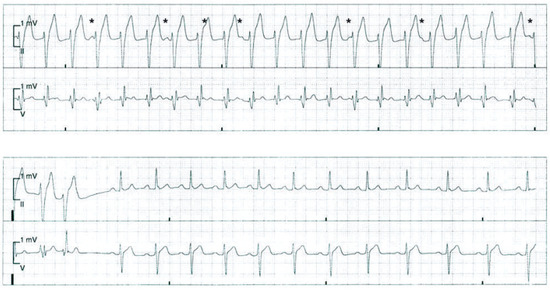

Nach einem erfolglosen Valsalva-Manöver sowie einer Carotis-Sinus-Massage wurde fraktioniert 10 mg Metoprolol intravenös verabreicht. Dadurch konnte jedoch keine Senkung der Frequenz erreicht werden, sodass der Patient zur weiteren medikamentösen Therapie der Tachykardie auf die Überwachungsstation verlegt wurde, wo unter Monitor-Kontrolle ein intravenöser Bolus von 12 mg Adenosin appliziert wurde. Auch darunter kam es zu keiner Terminierung der Tachykardie. Erst nach der Gabe von 5 mg Verapamil intravenös konnte die Tachykardie schliesslich terminiert werden (Abb. 2). Während der anschliessenden Überwachung war der Patient allezeit hämodynamisch stabil und im EKG zeigte sich ein normokarder Sinusrhythmus.

Die rechtsschenkelblockartige Morphologie mit einer leicht verlängerten QRS-Dauer von 130 ms sowie der überdrehte Linkslagetyp deuten darauf hin, dass es sich in diesem Fall um eine idiopathische ventrikuläre Tachykardie aus dem linken posterioren Faszikel handelt, welche üblicherweise auf Verapamil anspricht. Der Arrhythmie liegt ein Reentry-Mechanismus im linken posterioren Faszikel zugrunde [1]. Aufgrund des Ursprungsorts in den Purkinje-Zellen des Faszikels ist die QRS-Verbreiterung nur wenig ausgeprägt (120 ms bis 160 ms). Selten entspringt die Tachykardie aus dem anterioren Faszikel des linken Schenkels und dann findet sich eine überdrehte Rechtsachse des QRS-Vektors. Das fehlende Ansprechen auf Adenosin ist als schwacher Hinweis und nicht als diagnostischer Test zu werten, dass es sich um keine supraventrikuläre Tachykardie im klassischen Sinne handelt. Im Tachykardie-EKG findet sich eine atrio-ventrikuläre Dissoziation, was den ventrikulären Ursprung der Tachykardie bestätigt (Abb. 2).

Abbildung 2.

Terminierung der Tachykardie unter Verapamil. Während der Tachykardie kann eine atrio- ventrikuläre Dissoziation dokumentiert werden. Die dissoziierten P-Wellen sind mit einem «Sternchen» gekenn- zeichnet.